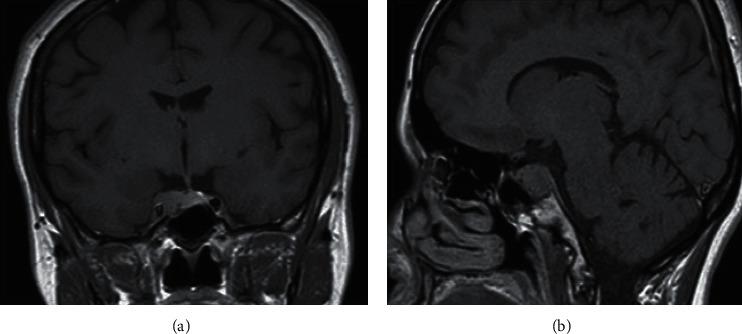

复发性库欣病患者的三次成功妊娠

Three Successful Pregnancies in a Patient with Recurrent Cushing's Disease.

The association of pregnancy and Cushing's disease (CD) is rare. A 28-year-old woman was admitted for clinical suspicion of Cushing's syndrome. The investigations confirmed the diagnosis of CD with secondary hypogonadotropic hypogonadism due to an invasive pituitary macroadenoma. The patient underwent transsphenoidal adenomectomy, and histopathology showed an adrenocorticotropic hormone pituitary adenoma. Initial remission of CD ensued, and fertility was restored as the patient had 2 uncomplicated pregnancies. Five years and 10 months after surgery, a third spontaneous pregnancy was confirmed with underlying recurrent CD. Having mild hypercortisolism, CD was managed expectantly. The outcome was a healthy full-term neonate with no maternal complications during pregnancy or labor. Our case highlights the challenge faced by physicians of choosing the optimal approach to active CD in pregnancy. In cases where maternal and fetal complications are mild, conservative approach may be used and specific treatment can be postponed until after delivery.

摘要

妊娠与库欣病(CD)的关联较为罕见。一名28岁女性因临床怀疑库欣综合征入院。检查确诊为CD,伴有因侵袭性垂体大腺瘤导致的继发性低促性腺激素性性腺功能减退。患者接受了经蝶窦腺瘤切除术,组织病理学显示为促肾上腺皮质激素垂体腺瘤。CD最初缓解,患者恢复生育能力并顺利经历了2次妊娠。术后5年10个月,确诊第三次自然妊娠合并复发性CD。鉴于存在轻度皮质醇增多症,对CD采取了观察等待的处理方式。结果是产下一名健康的足月新生儿,孕期及分娩过程中未出现母体并发症。我们的病例凸显了医生在为孕期活动性CD选择最佳治疗方法时面临的挑战。在母婴并发症较轻的情况下,可采用保守方法,将特定治疗推迟至分娩后进行。